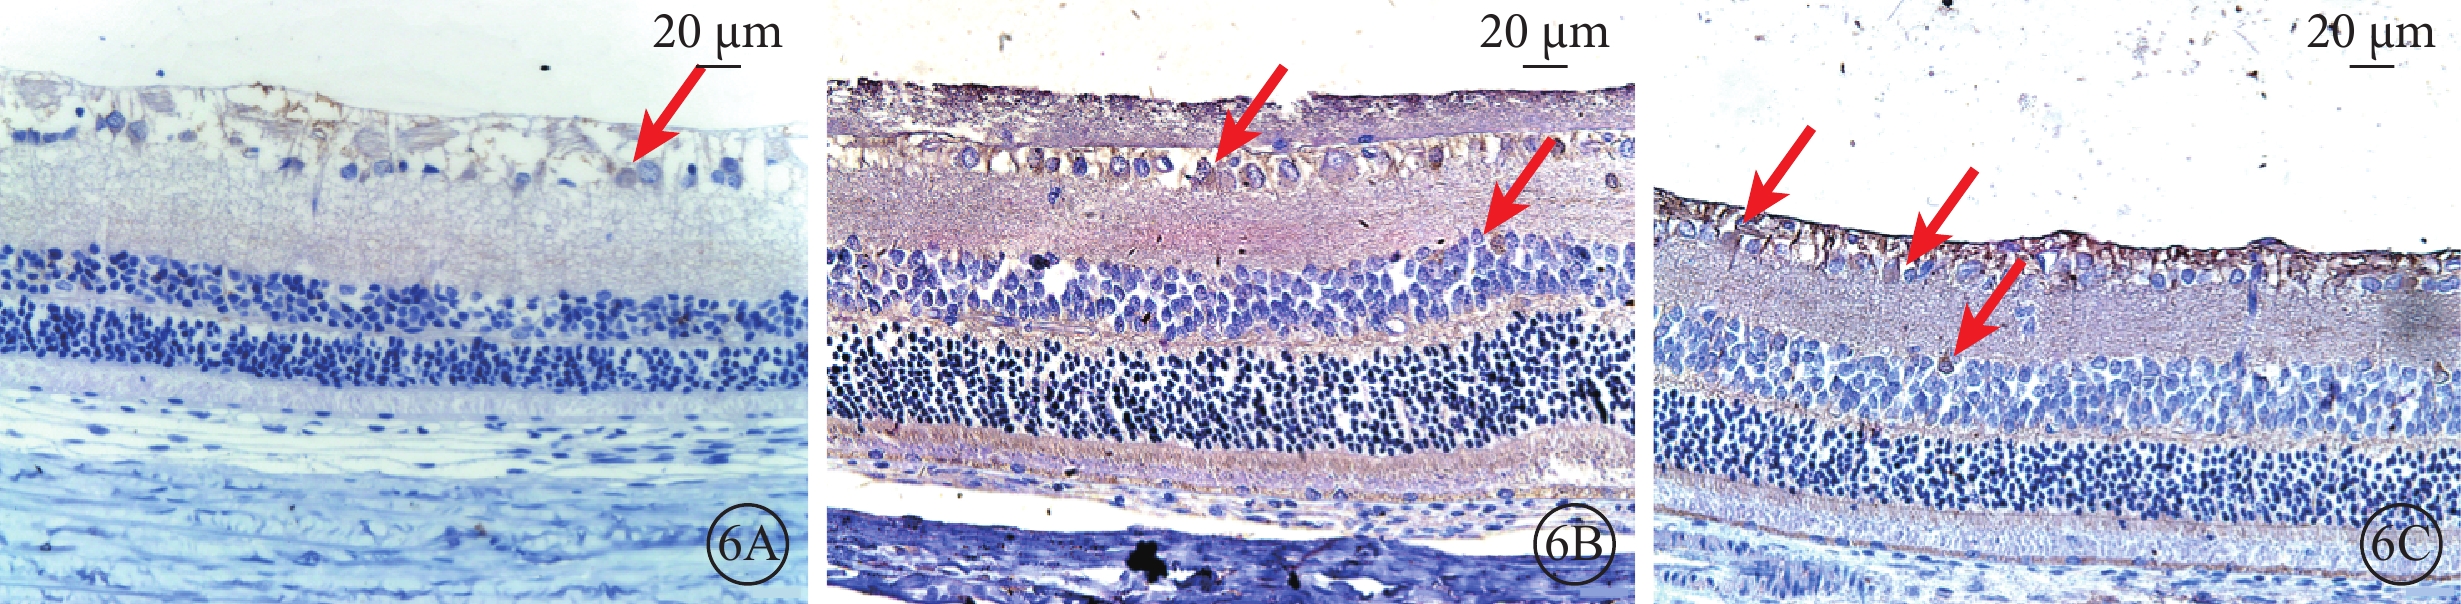

假手術組大鼠視網膜各層均可見Nrf2+細胞,胞漿呈棕黃色。建模后12 h,RIRI組、NAS組大鼠視網膜GCL、INL均可見較多Nrf2+細胞,細胞核呈棕黃色(圖6)。假手術組大鼠視網膜Nrf2+細胞數為(184.27±20.49)個/mm2;建模后12 h,RIRI組、NAS組大鼠視網膜Nrf2+細胞數分別為(389.67±43.76)、(565.89±77.34)個/mm2。RIRI組大鼠視網膜Nrf2+細胞數明顯多于假手術組,差異有統計學意義(F=170.354,P<0.01);NAS組大鼠視網膜Nrf2+細胞數明顯多于RIRI組,差異有統計學意義(F=51.122,P<0.01)。

Nrf2/HO-1信號通路在調控炎癥反應及氧化應激中占有重要地位。研究發現,RIRI早期,炎癥反應可活化Nrf2/HO-1通路,表現為Nrf2被激活,由胞漿入核啟動下游的HO-1表達[14],進而可抑制TNF-α蛋白的表達,減輕炎癥反應[15]。本研究結果顯示,建模后12 h,RIRI組大鼠視網膜中Nrf2、HO-1蛋白表達較假手術組增加,結果與文獻報道結果一致[16]。Yoo等[17]發現,NAS可促進氧化應激引起的小鼠海馬神經元細胞中Nrf2核轉位,激活Nrf2信號通路,對海馬神經元發揮神經保護作用,但NAS經Nrf2/HO-1通路對視網膜的保護作用尚未見報道。本研究Western blot檢測結果顯示,NAS組大鼠視網膜中Nrf2、HO-1蛋白水平均高于RIRI組;免疫組織化學染色結果也顯示NAS組大鼠視網膜胞核內Nrf2+、HO-1+細胞數多于RIRI組。這提示在RIRI中,NAS可通過促進視網膜Nrf2核轉位,上調Nrf2、HO-1蛋白的表達,進而抑制TNF-α蛋白表達水平,從而減輕RIRI。為進一步驗證此結果,本研究對建模后12 h時RIRI組、NAS組大鼠視網膜TNF-α+細胞數差值與Nrf2+、HO-1+細胞數差值進行相關性分析,發現兩組TNF-α+細胞數差值均與Nrf2+、HO-1+細胞數差值呈負相關,提示NAS可能通過Nrf2/HO-1通路抑制RIRI大鼠視網膜中TNF-α蛋白表達,從而減輕RIRI,發揮保護作用。